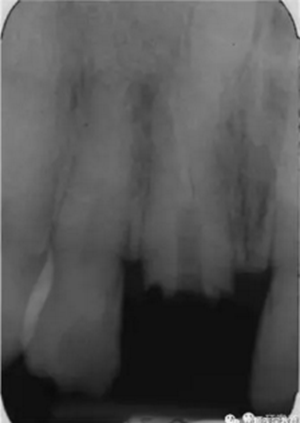

本例患者為男性,53歲,由于右上頜中切牙疼痛,在蘇格蘭的格拉斯哥口腔醫(yī)院就診。根管治療后1年來(lái)牙齒出現(xiàn)自發(fā)性疼痛。檢查發(fā)現(xiàn)患者冠部修復(fù)體3周前丟失,未發(fā)現(xiàn)竇道,牙面較多部位探診時(shí)患者較敏感,說(shuō)明牙齒仍為活髓,可以修復(fù)。患者身體狀況良好。影像學(xué)顯示,患牙根尖彎曲處充填不充分,根尖周有陰影,還發(fā)現(xiàn)在右上頜中切牙的根尖部有一倒置的額外牙顯影,周?chē)乐苣挾日!?/p>

圖1. 治療前患牙根尖周顯影